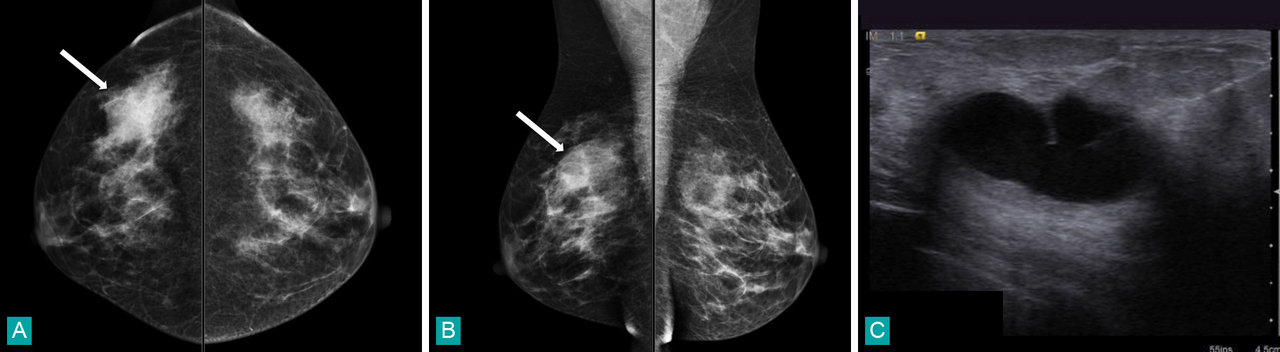

Patiente âgée de 46 ans ayant une masse palpable douloureuse du quadrant supéro-externe du sein droit. Les incidences de mammographie sont lues "en miroir" pour détecter plus aisément une asymétrie de densité mammaire. Par convention, le sein droit est disposé à gauche, sur les incidences de face, la partie externe du sein se projette en haut du cliché, en oblique, c'est la partie supérieure du sein qui se projette en haut du cliché. On identifie aussi bien sur les incidences en compression crânio-caudale (face) [fig. A] qu'en latéral-oblique (fig. B) une asymétrie de densité glandulaire du quadrant supérieur et externe du sein droit (flèche). Cette anomalie se traduit en échographie (fig. C) par un volumineux kyste (masse anéchogène renforçant le faisceau ultrasonore). Notez sur l'image d'échographie la visualisation d'une aiguille de ponction sur la droite.